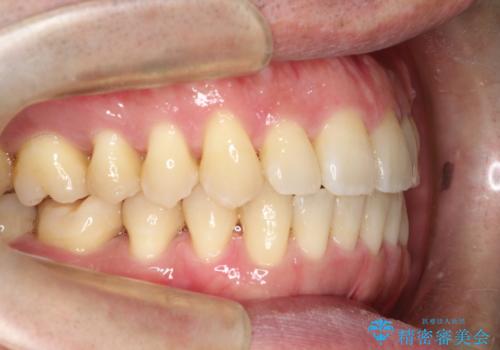

ワイヤーによる全体的ながたつきの矯正治療

- 30代男性

- メタル

- 1年3ヶ月

- 全体的ながたつきを治したいとのことで来院されました。

ワイヤー矯正とマウスピース矯正の二つの器具での治療をご案内し、ワイヤー矯正を選択されました。

インビザラインを装着するのがめんどうなので、ワイヤーの方があっているとのことで今回の治療方法を選択されました。